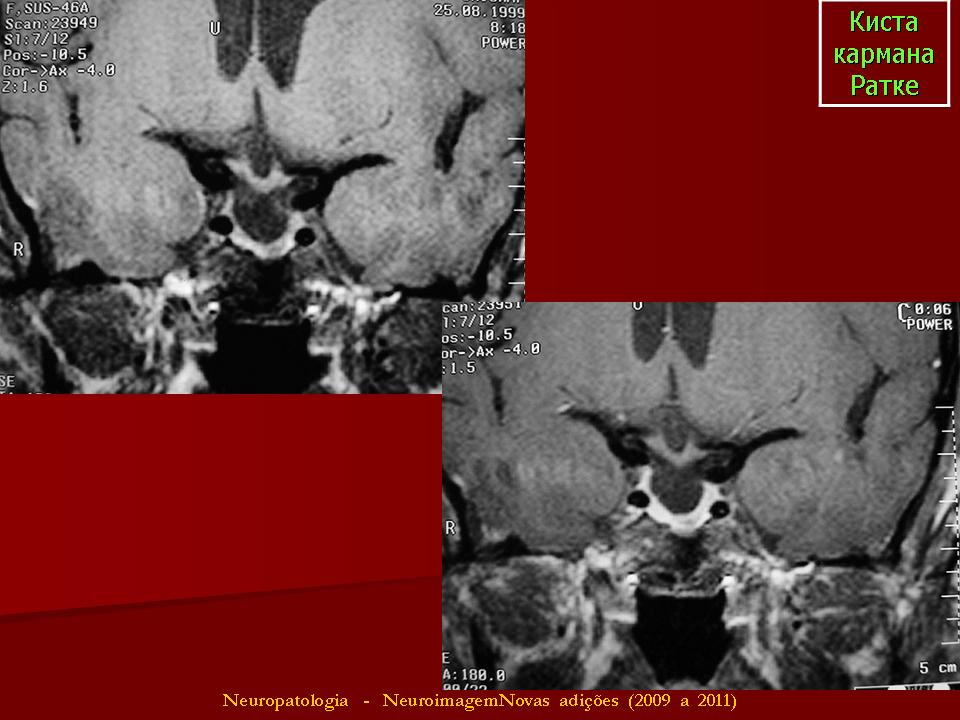

ГМ. Киста кармана Ратке. +

Киста кармана Ратке

Отличные изображения, спасибо. И хорошо что тут стрелочками указана киста и аденогипофиз, который всегда деформирован кистой и киста непосредственно к нему прилижет.

Киста кармана Ратке ИМХО должна иметь стенку. На первой серии снимков верхней стенки нет и киста сливается с супраселлярной цистерной, имеет неотличимые от ликвора сигнальные характеристики. Насчёт подстверждения. Вот интересно мне, как можно подтвердить кисту кармана Ратке в данном случае?? Гистологически?

Мне тоже показалось, что в первой серии изображений кистой и не пахнет.Видится "пустое" турецкое  седло с расширенной  супраселлярной цистерной.Оказалось, что не только мне одной.